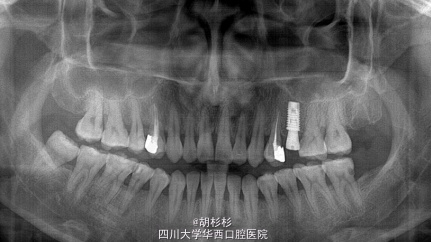

诊断:25牙残根 处理:拔除25牙的同时植入种植体

发这个病例的目的是一个反面的例子,反面在只用了全景指导种植手术,是非常危险的,常规来说一定要在术前拍三维的cbct,特别是上颌后牙与上颌窦底的关系非常密切,不确定精确的骨高度,对经验不足的医生来说很容易穿孔,造成术后的严重并发症。(病例来自网络)